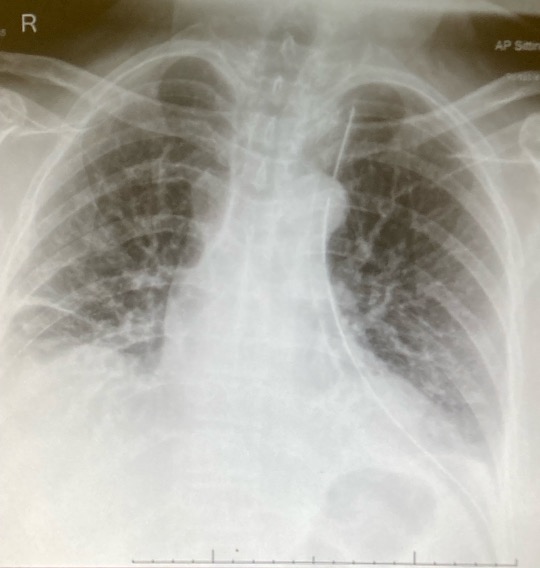

Postoperatively, the chest drain was removed at six hours (Figure 5), and the patient was discharged 20 hours after the operation on postoperative day one (Figure 6). The patient experienced no postoperative complications and had an uneventful postoperative recovery.

Figure 5: An image of the postoperative CXR with the drain in.